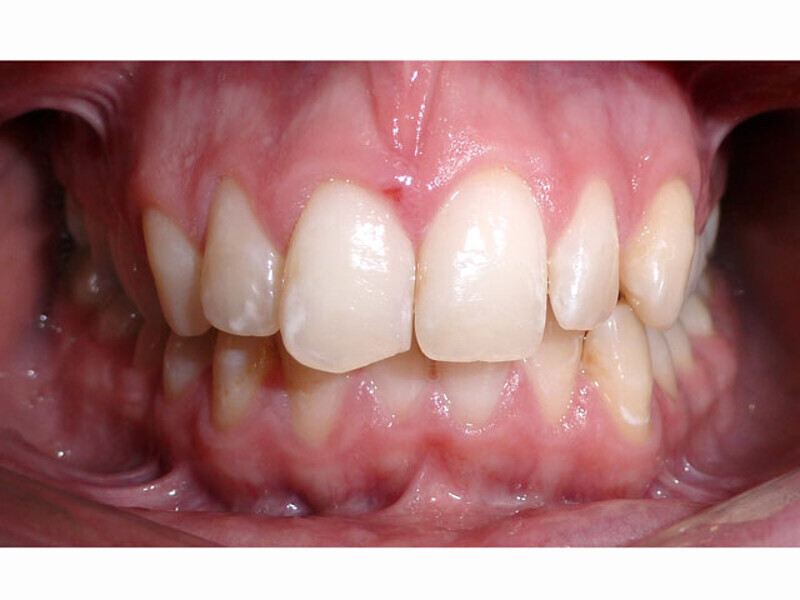

ClearCorrect treatment of crowding